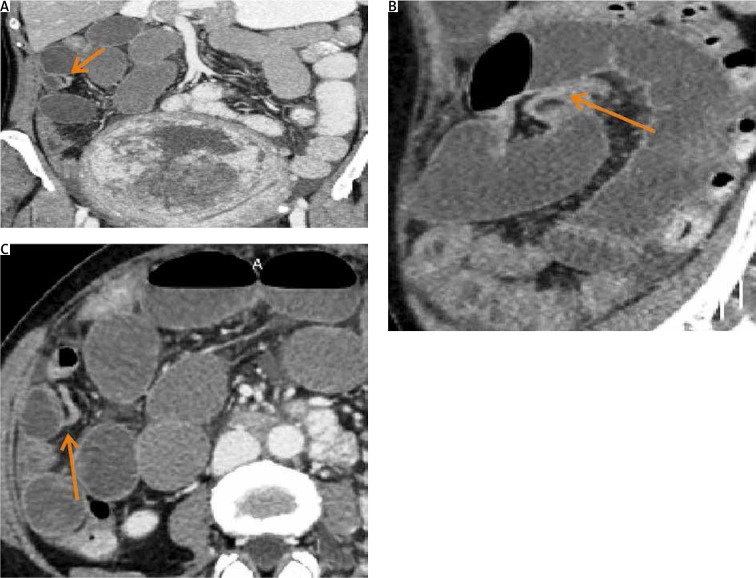

小肠梗阻(SBO)是一种严重的疾病,有明显的症状,如便秘、呕吐和腹胀。它通常是由公认的因素引起的。成像技术和微创手术的最新进展大大提高了我们准确选择手术干预患者和迅速识别常见SBO原因的能力。然而,认识到诊断罕见的SBO病因仍然是一项挑战,这一点至关重要。我们报告一个罕见的病例机械性肠梗阻由巨大的子宫肌瘤引起的44岁妇女。大子宫肌瘤可引起机械性小肠阻塞,虽然这不是常见的原因。诊断成像,特别是计算机断层扫描,在诊断和确定适当的管理计划中起着至关重要的作用。准确的监测和成像可以通过避免不必要的手术干预和降低发病率和死亡率来改善患者的预后。治疗方法包括内科和外科两种。这两种方法都被证明是有效的,如果药物治疗不成功,外科手术是最后的手段。这些手术方法的准确性和有效性已显示出良好的结果和显著的预后益处。识别和报告罕见的肠梗阻原因对于提高未来的认识和提高患者的预后是至关重要的。

Small bowel obstruction (SBO) is a serious condition with distinct symptoms such as constipation, vomiting, and abdominal distension. It is commonly caused by well-recognised factors. Recent advancements in imaging techniques and minimally invasive procedures have significantly improved our ability to accurately select patients for surgical intervention and promptly identify common SBO causes. Nonetheless, it is crucial to recognise that diagnosing rare SBO causes remains a challenge. We present a rare case of mechanical bowel obstruction caused by massive uterine fibroids in a 44-year-old woman. Large uterine fibroids can cause mechanical small intestine obstruction, although this is not a common cause. Diagnostic imaging, particularly computed tomography, plays a crucial role in diagnosing and determining appropriate management plans. Accurate monitoring and imaging can lead to improved patient outcomes by avoiding unnecessary surgical intervention and reducing morbidity and mortality rates. Treatment options include both medical and surgical methods. Both approaches have proven effective, with surgical procedures being the last resort if medical treatments are unsuccessful. The accuracy and efficacy of these surgical methods have shown promising results and significant prognostic benefits. It is critical to identify and report rare causes of bowel obstruction to improve future recognition and enhance patient outcomes.